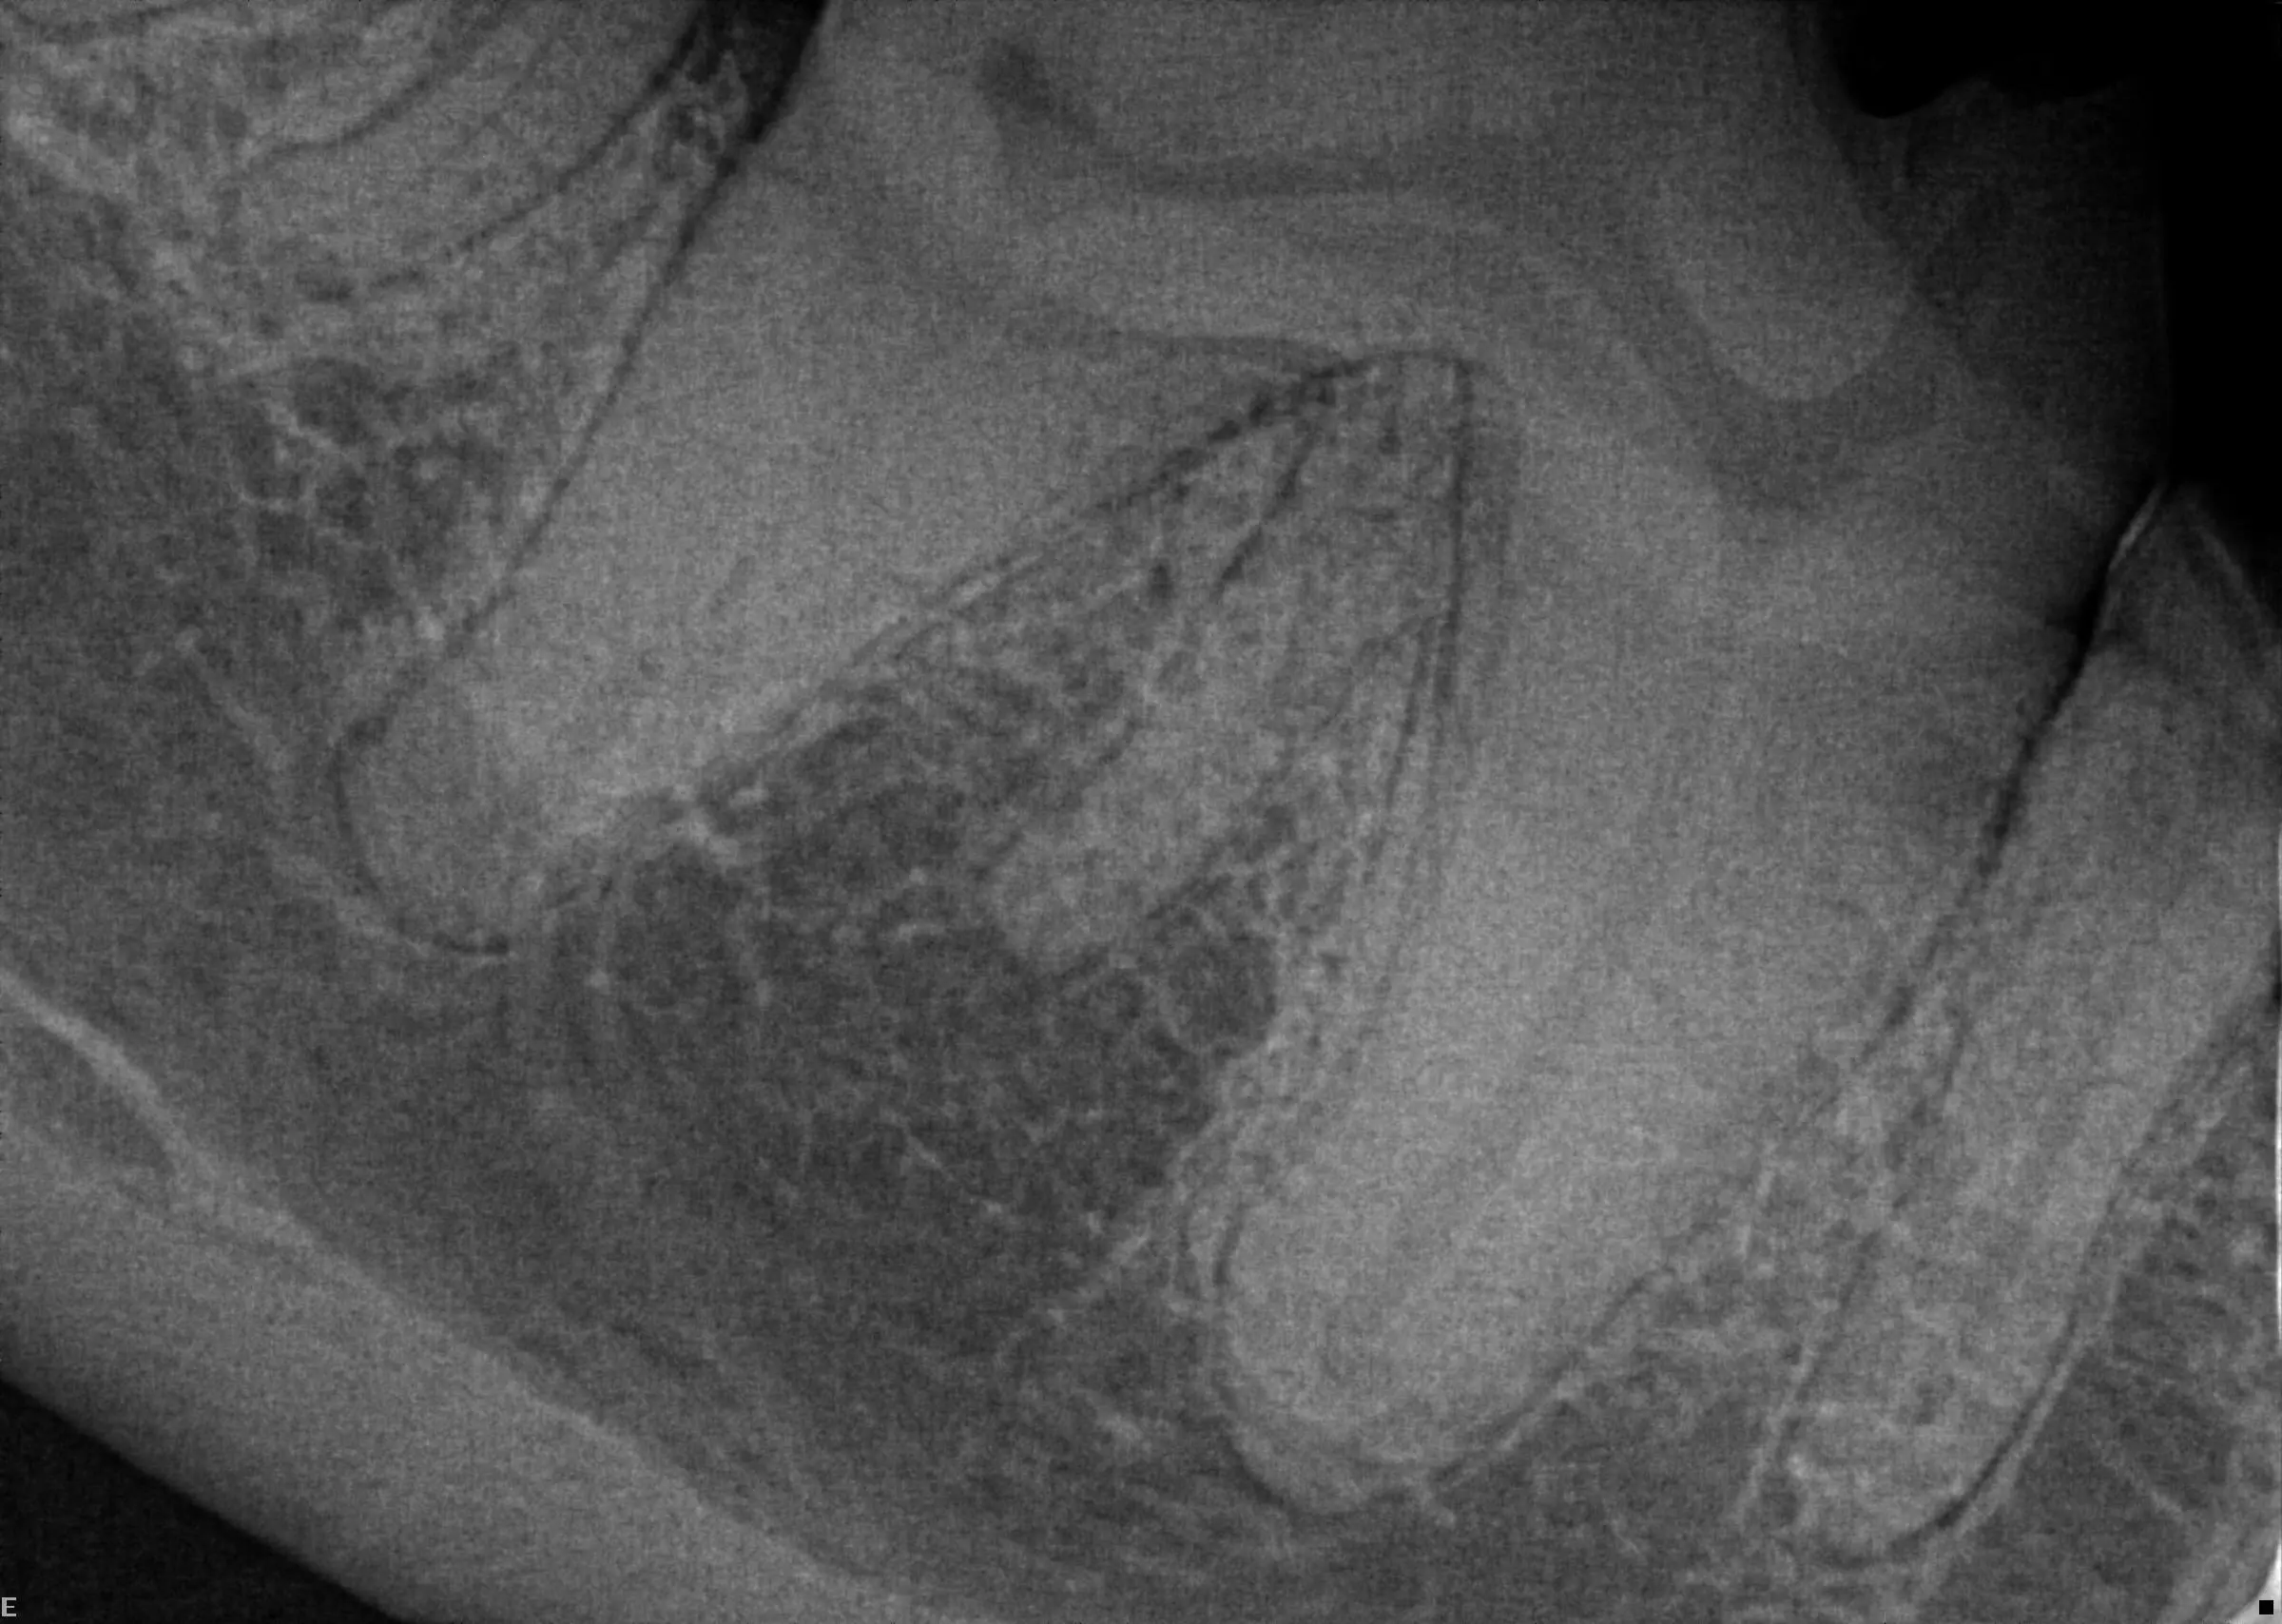

Here is a tooth I radiographed recently that has an accessory root (central). While the tooth does not show any pathology, I did note it in the pet’s dental record. If I have to treat this tooth in the future, it is important to know this fact.